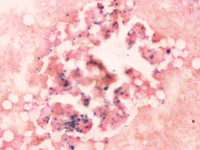

Figure c. Bone marrow aspirate smear 100X, Giemsa stain showing Gaucher like cell in AML.

Gaucher like cell in AML.